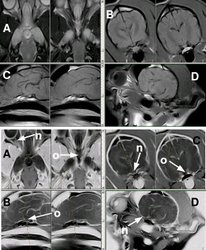

Vía óptica. Cocker. Nervio óptico (n), quiasma óptico (o) Se muestran 4 secuencias de resonancia magnética, en positivo (las de arriba) y en negativo (las de abajo) A: SE T2 dorsal. B: SE T1 transversal. C: SE T1 sagital. D: SE T1 oblícuo, siguiendo la trayectoria del nervio óptico izquierdo, del cual se visualiza perfectamente su entrada por el agujero óptico del esfenoides.